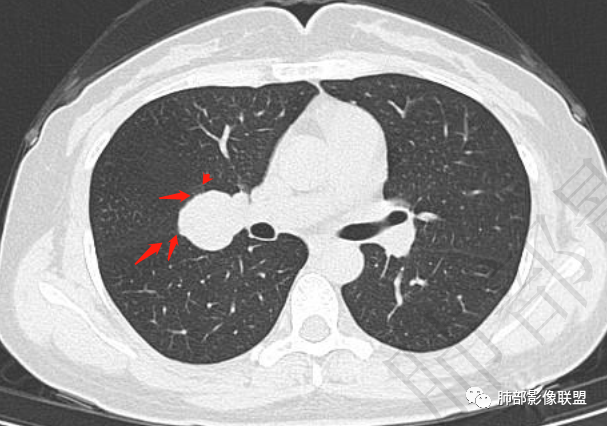

右肺门类圆形实性肿块,边缘光滑,无分叶毛刺,跨叶,推移血管,密度均匀,增强延迟强化相对明显,未见坏死及血管造影征。

右肺门区类圆形肿块,跨叶,边缘光滑,密度均匀,血管贴边,推移,延迟强化,考虑PSP,鉴别CD

鉴别诊断:PSP、SFT类癌,肿块主要与血管关系密切,与气管关系不大,故类癌可能性小,肿块渐进性均匀强化,可见血管贴边征、肺动脉为主征,中年女性患者,首先考虑PSP,肿块与叶间裂关系比较密切,不能除外SFT,但与血管关系更为密切,SFT往后排一下。

跨叶裂,类圆形,有浅分叶,血管好像来源于肺动脉

3.病灶密度均匀,未见液化坏死、钙化及脂肪低密度。轻度强化,可见纤细血管影蜿蜒穿行。右肺动脉推移变形,未见侵入或充盈缺损。

4)发生于肺表面(近脏层胸膜或叶间裂),强化不显著,可见穿行血管,与本例的符合程度是最高的。